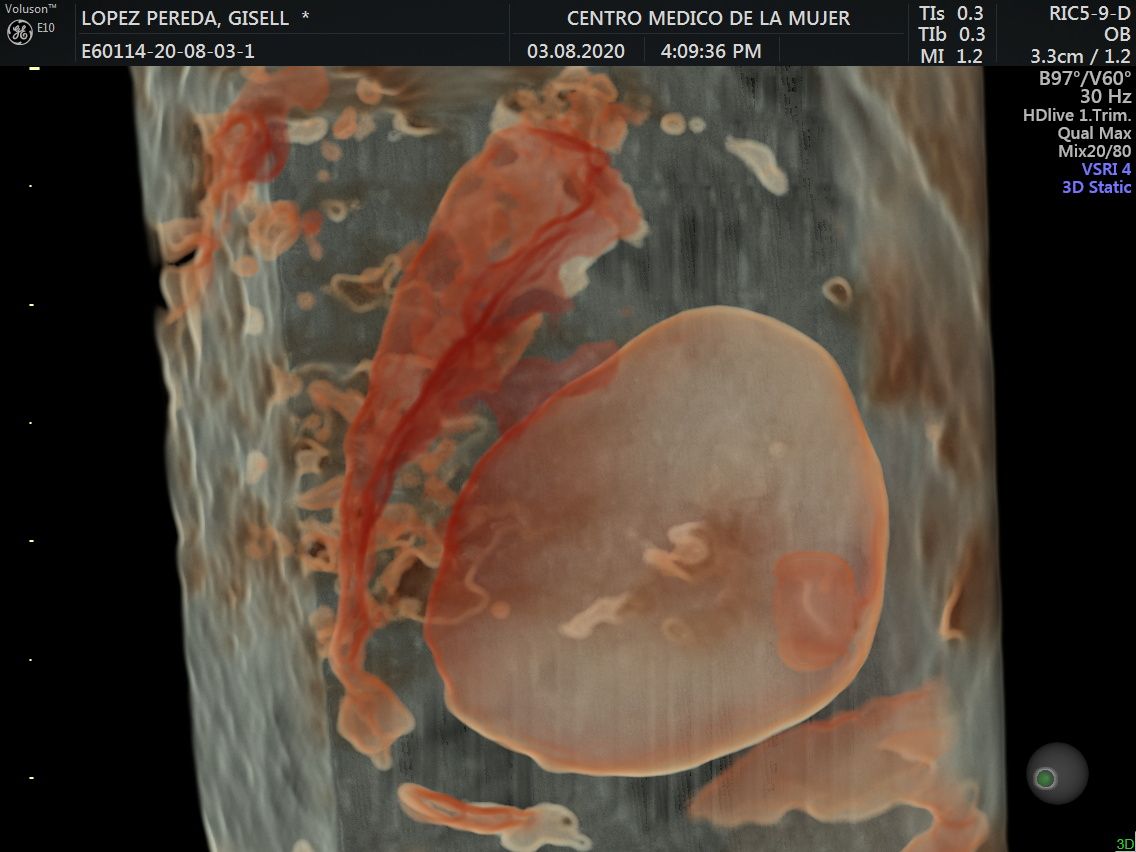

Fotos y videos

ECO Anatómico

Consiste en la evaluación especifica de cada organo y sistema del bebé con medidas detalladas de cada parte para evaluar su crecimiento proporcional.